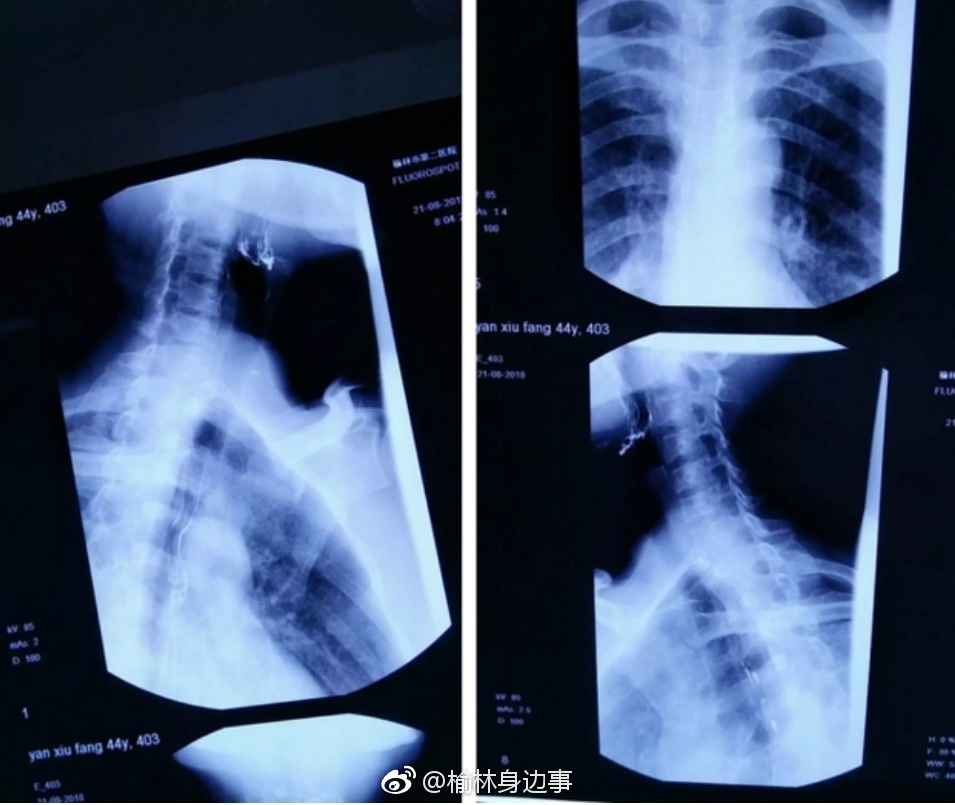

一根鸡骨头卡喉咙 竟让她差点瘫痪

小小一根鸡骨头卡喉咙,竟让她差点瘫痪